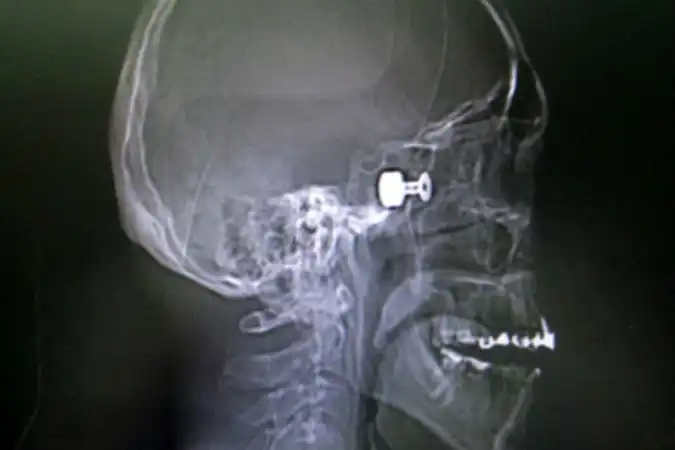

Сначала раненного доставили в глазной центр, где врачи удалили глазное яблоко. Потом перевели в краевую больницу. Отолорингологи краевой больницы провели, по сути, уникальную операцию высокотехнологичную операцию, чтобы извлечь из головы пациента пулю размером с орех. Самое опасное, что она находилась прямо в миллиметре от мозга молодого мужчины.

- Инородный предмет врачи ювелирно удалили под микроскопом, с применением эндоскопа через носовое отверстие, — рассказали в пресс-службе Краевой клинической больницы. — В настоящее время состояние пациента не вызывает у врачей опасений за его жизнь.